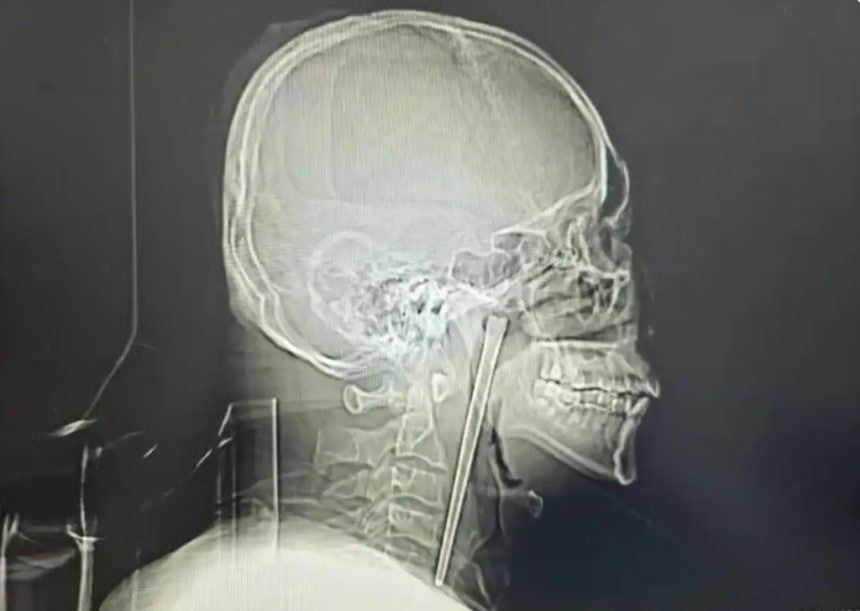

19일(현지시각) 사우스차이나모닝포스트(SCMP)는 왕씨가 이달 초 중국 북동부 랴오닝성 다롄시 중앙병원에서 목에 박힌 금속 젓가락을 제거하는 수술을 받았다. 보도에 따르면 왕씨는 8년 전 식사 도중 술을 마시다 실수로 금속 젓가락을 삼켰다.

사진 = 바이두 캡처

정밀 검사 결과 왕씨가 삼킨 젓가락은 목 안쪽 연구개 부위에 박혀 있었던 것으로 확인됐다. 의료진은 기적적으로 주변 점막에 손상이 없고 성대 기능 역시 정상적으로 유지되고 있었다고 설명했다.

왕씨는 목 절개를 거부했고 의료진은 구강을 통한 최소 침습 수술을 진행했다. 다행히 젓가락은 성공적으로 제거됐다. 왕씨는 빠르게 회복 후 수일 뒤 퇴원했다.